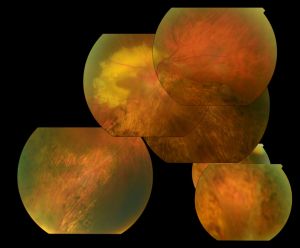

Optically empty vitreous on slit-lamp exam with avascular vitreous strands and veils is the defining characteristic of Wagner syndrome. Other associated findings include mild to severe myopia, presenile cataract of varying type, and varying degrees of night blindness secondary to associated progressive chorioretinal atrophy. Retinal traction and detachment can occur in advanced disease.[1] Uveitis has also been described in some cases.[1][4][5][11]

Nonspecific changes of the retinal pigment epithelium and overlying retina may also occur. These changes include but are not limited to pigment condensation, vascular sheathing, pigmented lattice degeneration, and peripheral chorioretinal atrophy.[1]

Some other occasional ocular features include spherophakia, ectopic fovea, synchysis scintillans, optic atrophy, and exudative vitreoretinopathy. No systemic abnormalities are associated with Wagner syndrome.[1][3][4][5][6]